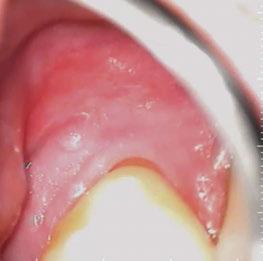

Palpate parotid, submandibular, and sublingual glands for enlargement, tenderness, or firmness (Figure 1).

Figure 3: Intraoral vestibule exam

Intraoral exam

Thorough inspection of the lips, buccal mucosa, gingiva, hard/soft palate, tongue (dorsal, lateral, and ventral), and oropharynx. Use gauze to pull and manipulate the tongue for complete visualization (Figures 3-4).